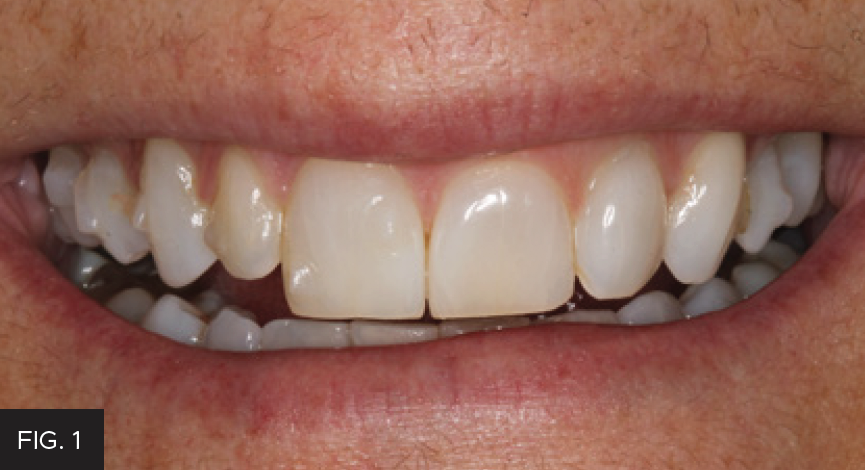

CLINICAL EXAMINATION AND FINDINGS

Examination and images, including the prescribed series of AACD photographs,2 revealed that #7 was normal, but smaller in crown size than ideal. Some tissue inflammation, likely related to orthodontic attachments, was visible on the tooth’s distal surface.The photographs and clinical data were reviewed with the patient. The main esthetic challenge would be to recreate incisal translucency and characteristics. (FIG 1 & 2)

Post-operative full smile view after orthodontic treatment completed and shows the completed composite restoration.